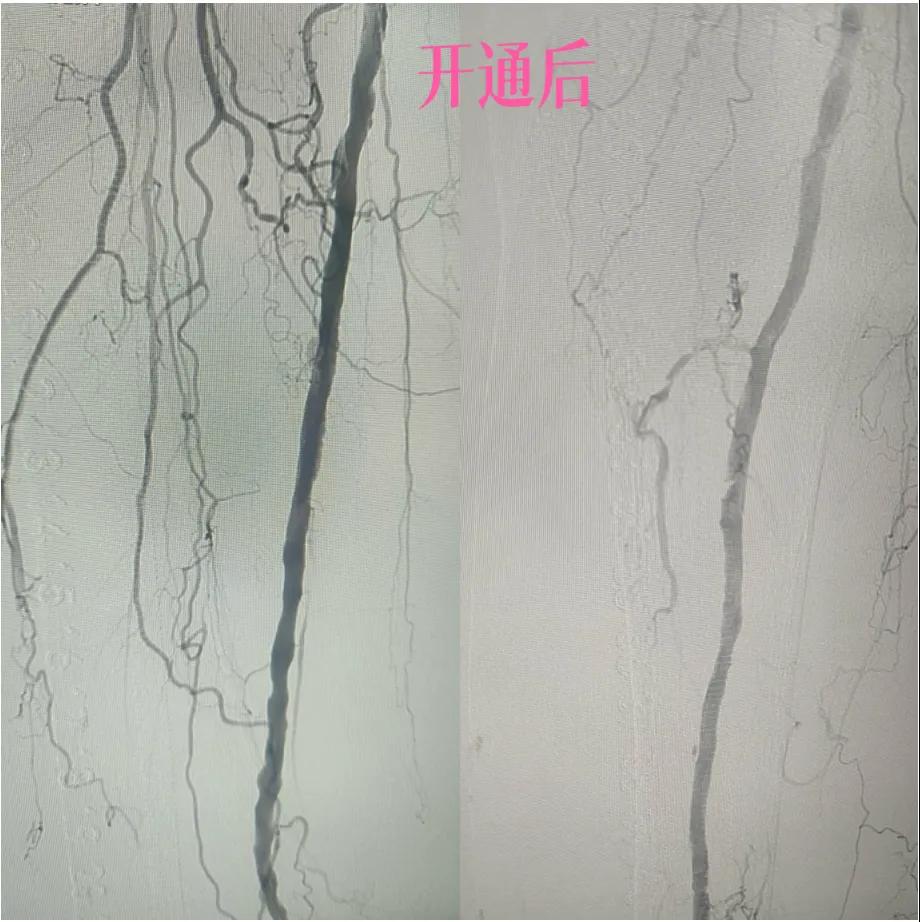

漯河市中醫(yī)院:微創(chuàng)介入:球囊擴(kuò)張術(shù),“撐”開生命通道

近日,漯河市中醫(yī)院外二科血管外科介入團(tuán)隊利用微創(chuàng)介入技術(shù)成功保住一患者患肢。

據(jù)悉,患者以“右足足趾疼痛伴第三足趾壞疽4月余”為主訴來院就診,查體患者右足第三趾末端呈壞疽狀,已結(jié)痂,足趾根部及足背部紅胖、壓痛,右側(cè)足背動脈,脛后動脈搏動未觸及,下肢深靜脈血管彩超:雙側(cè)下肢深動脈粥樣斑塊形成,右側(cè)腘動脈流速減低,右側(cè)脛后動脈及足背動脈不顯示(閉塞?)

為了挽救患者的患肢,避免截肢,外二科血管外科介入團(tuán)隊經(jīng)過縝密的術(shù)前討論和評估,決定采用目前微創(chuàng)介入技術(shù)——下肢動脈藥涂球囊擴(kuò)張成形術(shù)(DCB)。

2.  “探路”與“疏通”:在先進(jìn)的DSA(數(shù)字減影血管造影)設(shè)備實時引導(dǎo)下,猶如擁有了“透視眼”,導(dǎo)管導(dǎo)絲巧妙穿越病變血管的狹窄、閉塞段。這需要極高的技巧和對血管解剖的深刻理解。

3.  “球囊發(fā)力”:到達(dá)目標(biāo)閉塞段后,將未充氣的球囊導(dǎo)管送至病變部位。隨后,精準(zhǔn)控制壓力,使球囊緩慢充盈擴(kuò)張,如同在血管內(nèi)部進(jìn)行精細(xì)的“拓荒”,將堵塞的斑塊擠壓、塑形,撐開狹窄的血管腔。

4.  即刻“見證”:再次造影顯示,原本狹窄閉塞的血管段血流恢復(fù)通暢!足部遠(yuǎn)端血管顯影較前明顯改善。手術(shù)過程順利,患者靜息痛較前明顯改善。